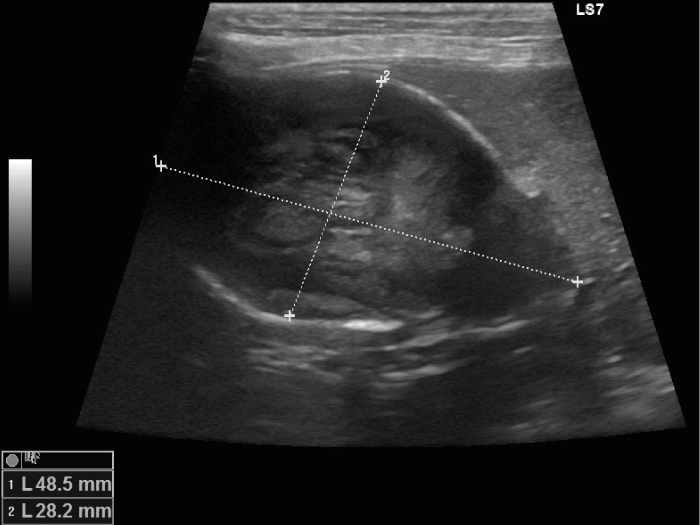

胆嚢粘液嚢腫の場合、エコー検査では放射状に胆泥が胆嚢壁に付着したキウイフルーツ状の所見が見られます。

エコーで胆嚢炎と胆嚢粘液嚢腫であることを確認し、破裂の危険性 を考えて腹腔鏡下胆嚢摘出術を実施することになりました。

臨床症状もなかったので腹腔鏡下胆嚢摘出術